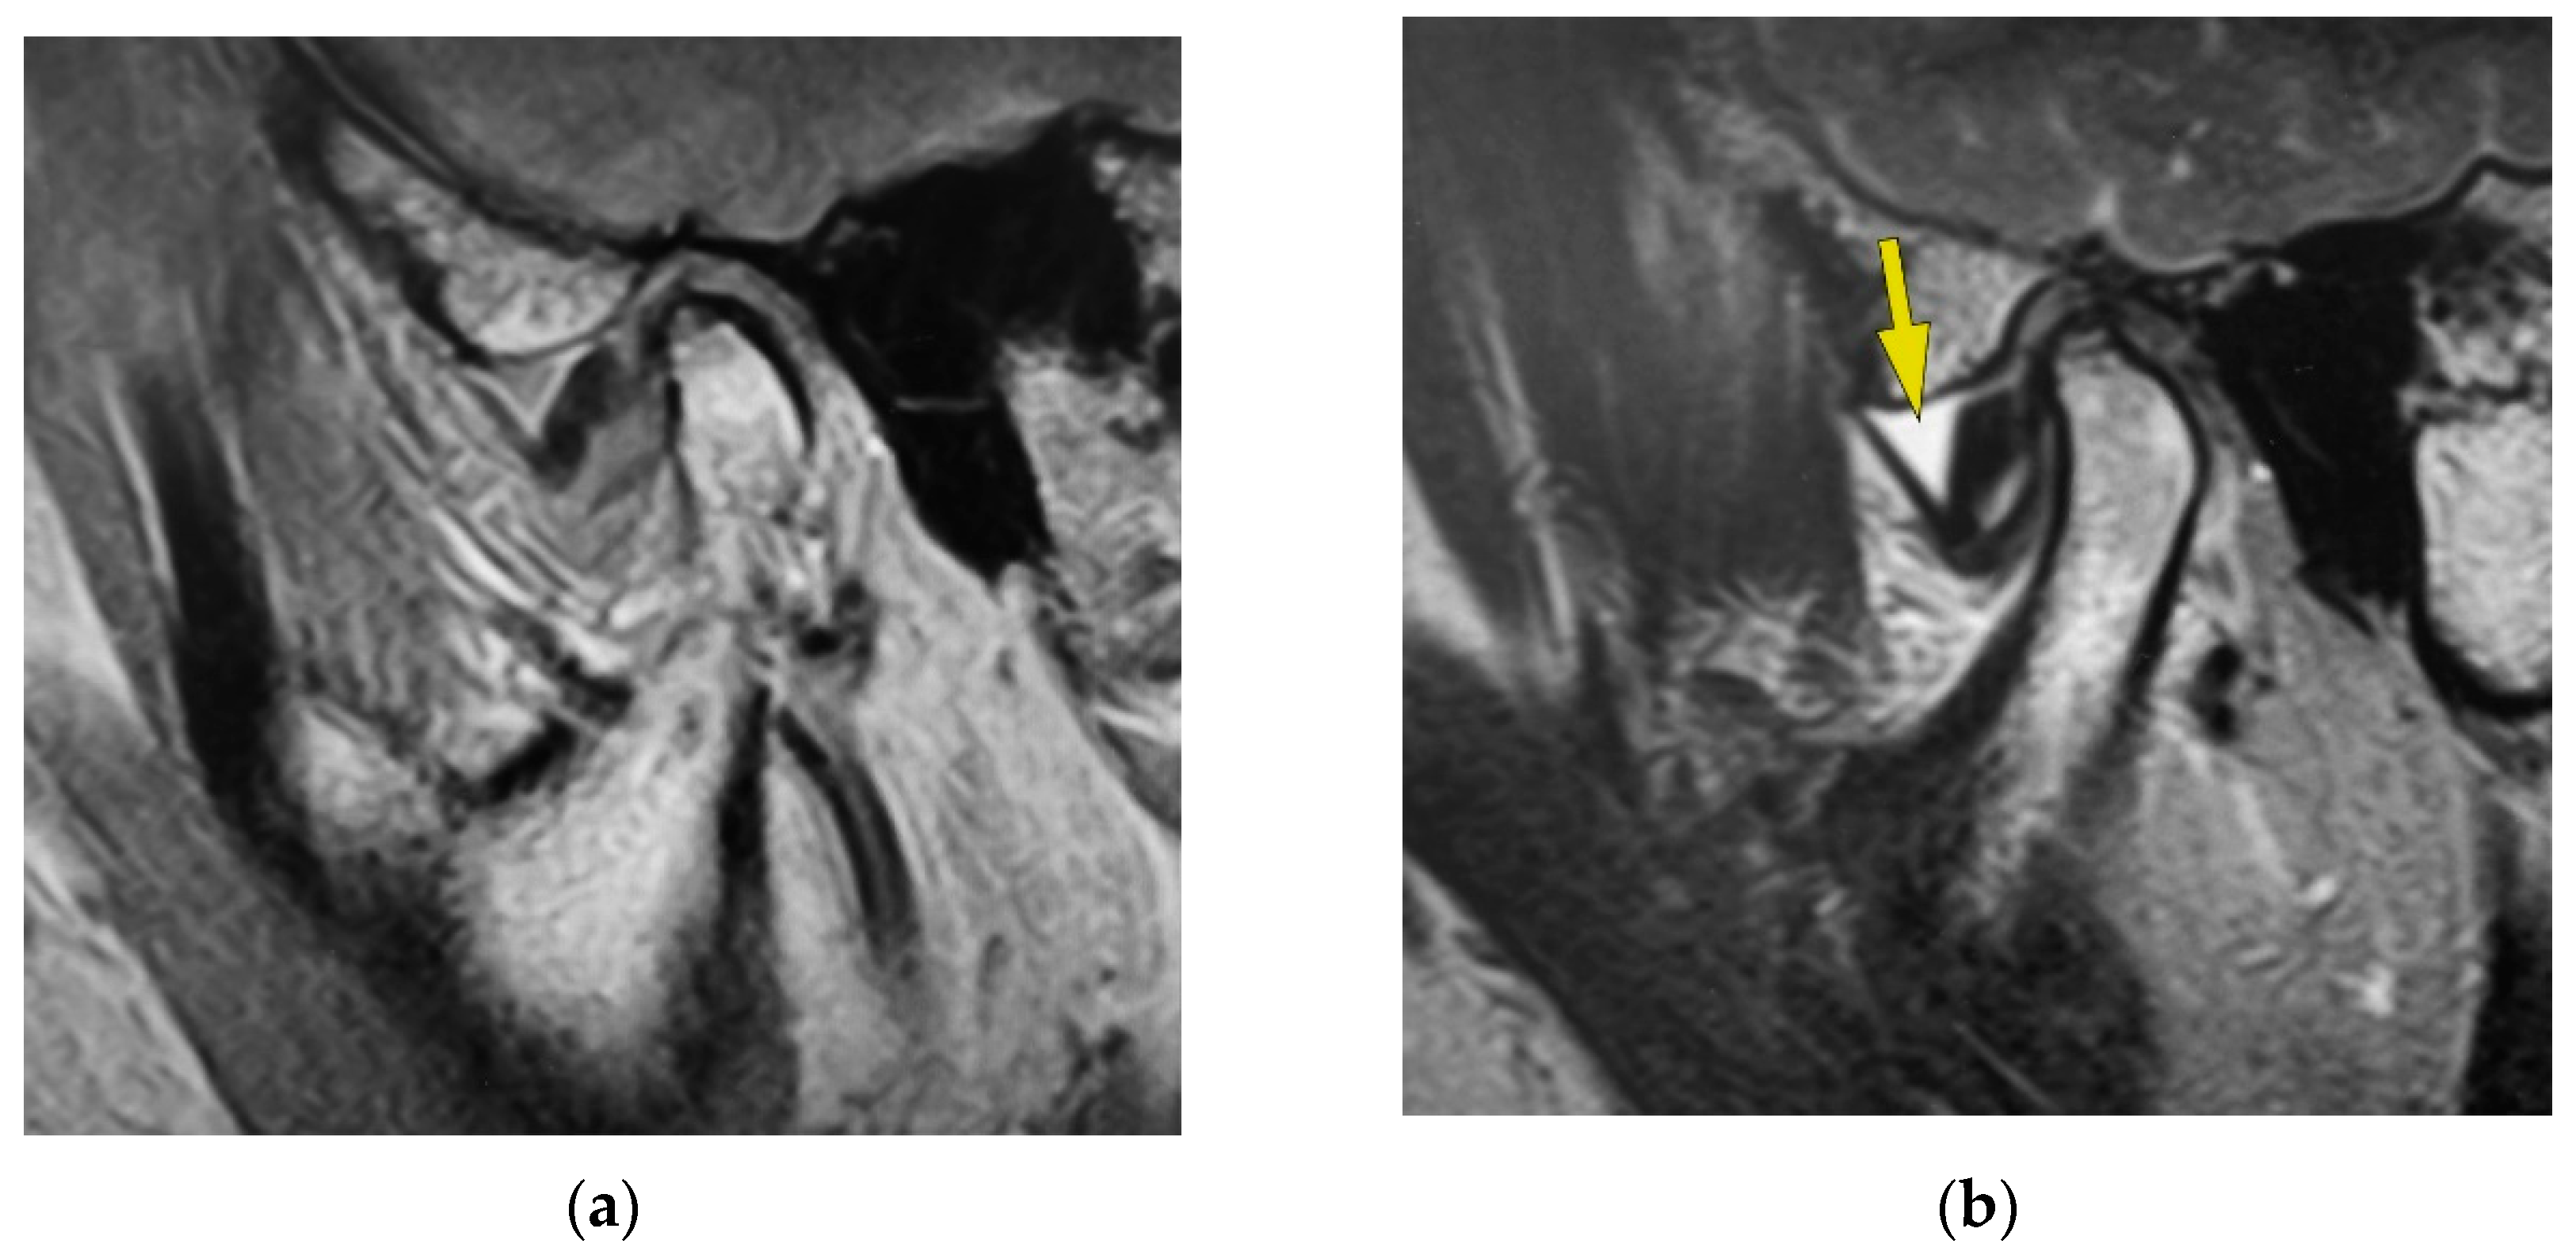

Examination for the Factors Involving to Joint Effusion in Patients with Temporomandibular Disorders Using Magnetic Resonance Imaging